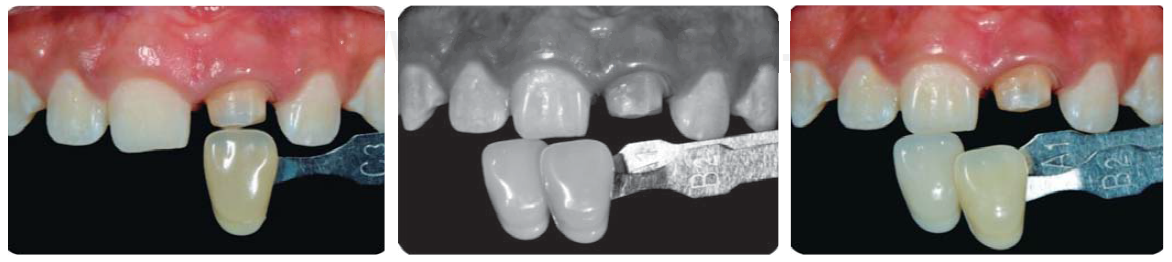

Registro del color

Con el colorímetro Chromascop ® (Figura 23) y provisionalización con resina bisacrílica Protemp 4 ® de 3M (Figura 24), se realiza el cementado de provisional con cemento RelyX Temp ® (3M ESPE), con la finalidad de ir conformando los tejidos previo a la cementación de la restauración final, de igual forma es importante acotar que el registro del color se realiza tanto del muñón de la preparación, como del diente homólogo para que el técnico protesista dental (TPD) tenga mayor información al momento de estratificar y de esta manera crear armonía con la elección de los tonos de las cerámicas a utilizar.

Registro de color y provisionalización

Con el colorímetro VITA classical ® y provisionalización con resina bisacrílica Protemp 4 ® de 3M, se cementa el provisional con cemento RelyX Temp ® (3M ESPE), manejando el tejido previo a la cementación de la restauración final. De igual forma es importante acotar que el registro de color se realiza tanto del muñón de la preparación (Figura 31 A), como del diente homólogo (Figuras 31B y 31C).